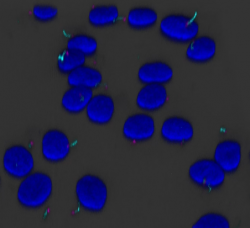

While the importance of primary cilia in the human body is now being recognized, rather little is known about the molecular mechanisms behind primary cilia function. For example, there are only a few signal transduction pathways that have been clearly attributed to primary cilia. One key to closing this knowledge gap is likely to be a detailed study of the dynamic protein composition of individual cilia. Therefore, the team behind the subcellular section of the Human Protein Atlas are currently leveraging the extensive antibody library of the Human Protein Atlas to systematically map proteins that localize to primary cilia of various cell types. The use of imaging-based spatial proteomics allows the study of detailed protein distribution at a single-cell level and in relation to cellular states.